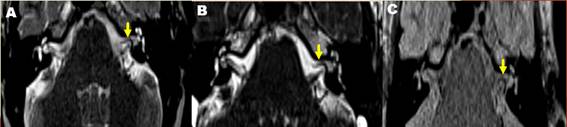

Se realizó una resonancia magnética nuclear (RMN) de oído interno mediante la que se observó un asa vascular en el ángulo pontocerebeloso izquierdo que ingresaba al conducto auditivo interno (CAI) en menos de 50 % de su longitud. Clasificación anatómica Chavda tipo II, formando un bucle entre el complejo del VII-VIII par craneal. (Fig. 1 y Fig. 2).

Según la clasificación anatómica (Chavda) las asas vasculares son de 3 tipos:

Tipo I: situada sólo en el ángulo pontocerebeloso, pero no entra en el CAI.

Tipo II: entra, pero no se extiende a >50 % de la longitud de la CA.

TIPO III: s e extiende> 50 % de la CAI.13,14,15